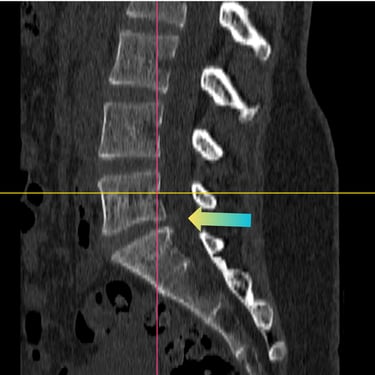

🧠 Fractura Vertebral Lumbar: Estabilización Segura con Fijación Transpedicular (FTP).

La fractura vertebral lumbar genera inestabilidad y dolor severo. La artrodesis con fijación transpedicular es una técnica quirúrgica eficaz que estabiliza la columna, previene desplazamientos vertebrales y mejora la recuperación funcional del paciente.